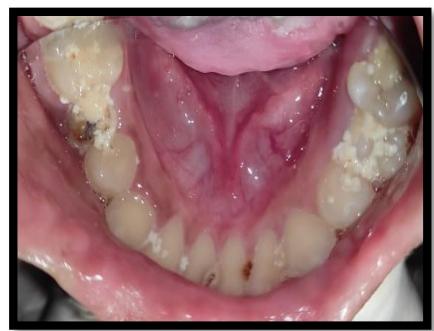

Intraoral examination revealed generalized attrition of teeth, early carious lesions in the posterior teeth with no complaints of sensitivity or pain, multiple areas of soft tissue scarring on the inner lips and buccal mucosa, no other visible pathologies or acute dental issues were noted as shown in Figure 2.

Figure 2: Intraoral examination (a&b) Multiple carious teeth, poor oral hygiene, (c&d) Diffused whitish mucosal lesions seen on the dorsal and ventral aspect of tongue, Labial soft tissue deformity of the patient due to biting